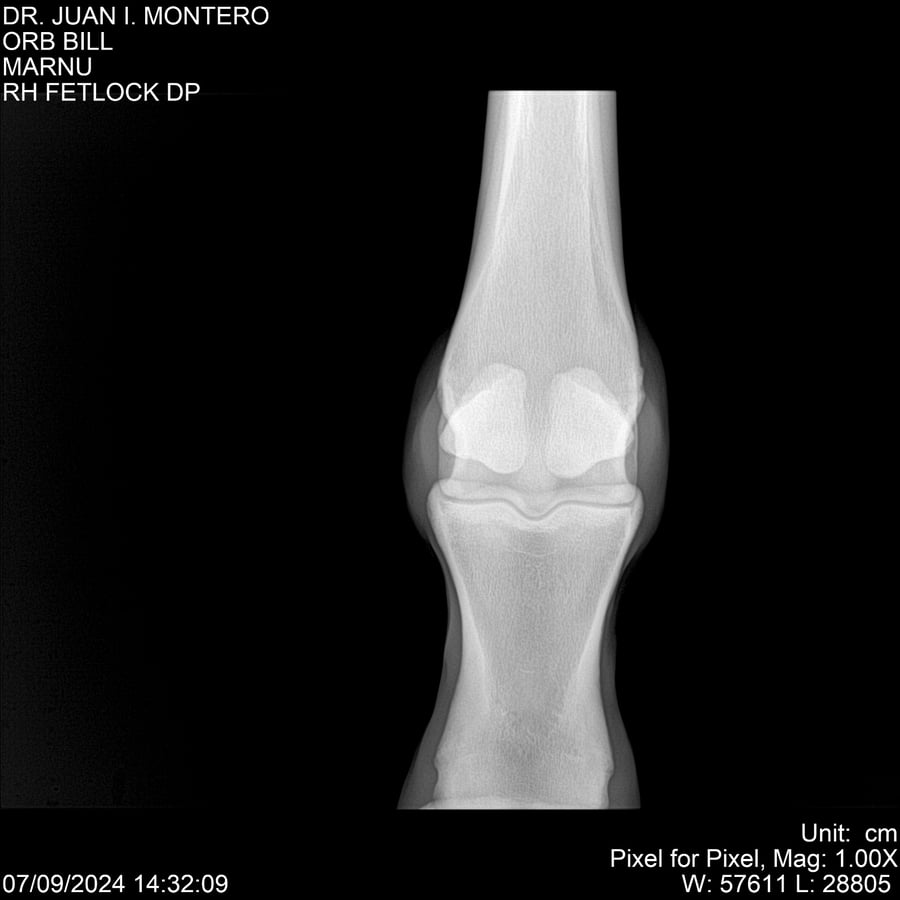

LOTE 7, ORB BILL 🔥 🔥 🔥 Lote Anterior Volver al remate Lote Siguiente Ficha Contacto Montevideo - Ficha del Lote Identificador: #282523 Categoría: Yeguarizos Montevideo - 83 Visualizaciones ClicData Contacto Empresa: Abelenda N. R., Walter Hugo Nombre*: Teléfono* : E-mail* : Mensaje Enviar Registrese gratis Este contenido Exclusivo está disponible sólo para usuarios registrados Ingresar